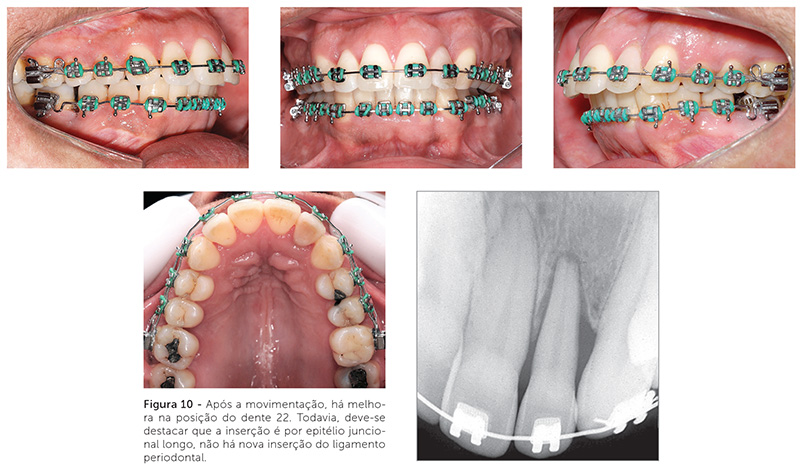

O tratamento ortodôntico de um paciente com doença periodontal não pode ser visto como um tratamento comum. Todos os casos ortodônticos exigem diagnóstico e planejamento efetivos, mas, em um paciente periodontal, esse exercício torna-se mais difícil. Deve-se ter em mente que todo tratamento deve beneficiar o paciente. Quando o periodonto está comprometido e há um planejamento ortodôntico falho, a chance do paciente ser prejudicado por um tratamento mal conduzido é grande. Por isso, esses casos exigem integração, de modo que o paciente não deve iniciar a movimentação ortodôntica sem a aprovação do periodontista, e esse deve acompanhar a situação periodontal durante todo o tratamento ortodôntico25,26. Um exemplo de movimentação dentária em paciente com pouca inserção periodontal pode ser visto nas Figuras 9, 10 e 11.

O tratamento ortodôntico de pacientes com doença periodontal controlada é, muitas vezes, um tratamento mais curto e direcionado. A redução do periodonto de suporte gera importantes implicações para o movimento dentário ortodôntico. Existe uma relação linear direta entre o suporte alveolar e a localização do centro de resistência. Conforme o osso alveolar de suporte vai sendo reduzido, o centro de resistência vai se movendo apicalmente. A intensidade e o ponto de aplicação de força durante o tratamento ortodôntico devem ser adaptados em tais situações. As forças utilizadas devem ser de magnitudes menores que aquelas utilizadas em periodontos saudáveis. Para que o movimento dentário seja mais controlado — haja vista que o centro de resistência encontra-se localizado mais apicalmente —, a colagem dos acessórios pode ser realizada mais gengivalmente.